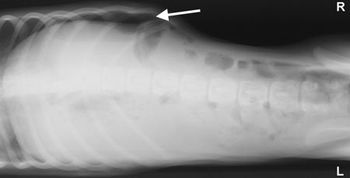

This case report describes the clinical signs and surgical treatment of an unusual hiatal hernia in a Chinese Shar-Pei.